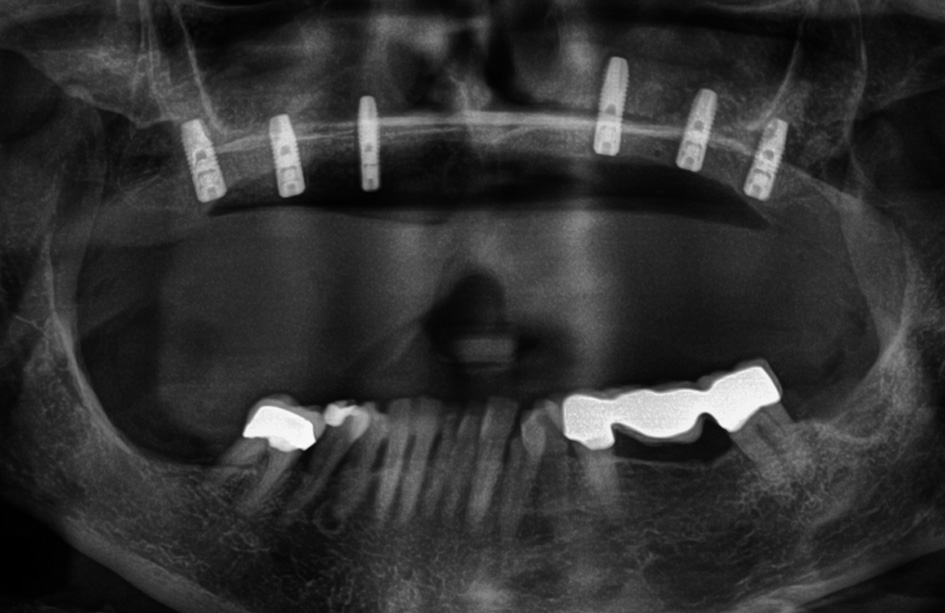

Vor dem zweiten OP-Eingriff nach 4 Monaten wurde im Labor eine Bohrschablone angefertigt. Zudem wurde ein DVT angefertigt, um im Sinne eines Backward planning die ideale Implantatposition planen zu können. Bei Eröffnung des augmentierten Kieferbereiches zeigte sich im augmentierten Bereich eine gute Regeneration und Revaskularisierung des Knochens (Abb. 14 bis 17). Sechs Implantate konnten somit in den augmentierten Bereich (Astratech EV®, DENTSPLY Sirona, Mannheim) mit ausreichender Länge und Durchmesser in Form einer gleichmäßigen Pfeilerverteilung in den Kieferknochen Inseriert werden (Abb. 18).

Großflächige Knochendefekte im parodontal vorgeschädigten Gebiss stellen chirurgische und prothetische Herausforderungen an den implantologischen Behandler [14, 2]. Im vorgestellten Fall erfolgte die Therapie der ausgedehnten Knochendefekte im Oberkiefer nach dem „biologischen Konzept“. Dabei werden die Knochenblöcke nach Entnahme entsprechend modifiziert und ausgedünnt. Die in der Dicke reduzierten Knochenscheiben werden auf Distanz gesetzt und der Zwischenraum zum Kieferkamm mit autologen Knochenpartikeln gefüllt [6, 7]. Nach vollständiger Abheilung des augmentierten Gebietes und Schaffung eines suffi zienten Knochenangebotes erfolgt die Implantation in möglichst gleichmäßiger Verteilung, um ein gutes Unterstützungspolygon und damit eine gute Kraftverteilung zu erreichen.